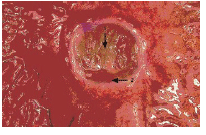

Возможно, большую опасность, чем собственно гипоперфузия, представяет «реперфузионное повреждение», приводящее к более грубому повреждению эпителиальных клеток ЖКТ. Этот феномен описан при непродолжительных, но повторяющихся эпизодах ишемии кишечника. Считается, что именно реперфузионное повреждение играет ведущую роль в формировании у больных синдрома острой неокклюзивной мезентериальной ишемии. Значительное повышение проницаемости слизистой оболочки, возникшее в ответ на ишемию и реперфузионные повреждения, приводит к ускорению абсорбции токсинов из просвета кишки [10,24,25,42,45,51,63]. При ишемии брыжейки возможно развитие субэпителиального отека слизистой оболочки кишечника и, как следствие, потеря эпителиальной выстилки верхушек ворсинок. При острой ишемии брыжейки с поражением стенки кишки высокая летальность обусловлена развивающимся при этом некрозом кишки и септическим шоком [16,31]. При более выраженной ишемии может иметь место трансмуральный некроз стенок органов ЖКТ (рис. 4,5).

Рис. 4. Постишемический некроз стенки желудка

Рис. 5. Язвенно-некротический колит